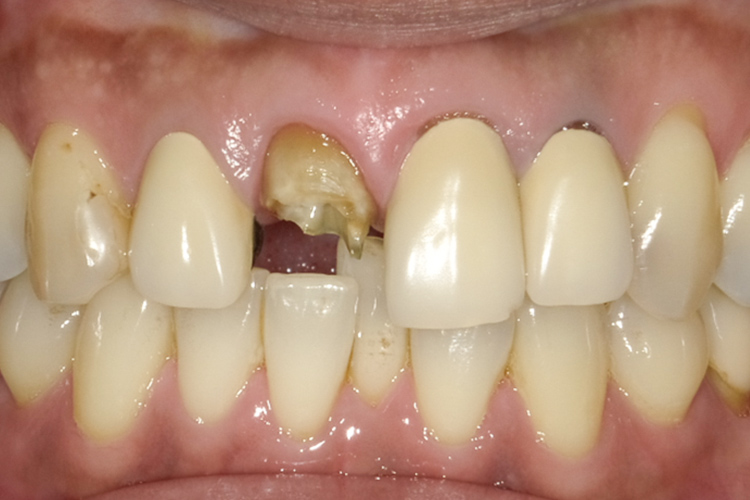

治療前

治療後